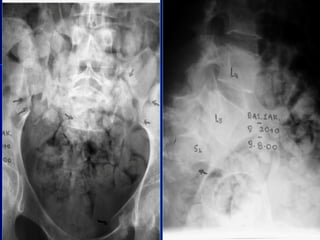

RRaaddiioollooggiiccaall

eevvaalluuaattiioonn

RRaaddiioollooggiiccaall ppaarraammeetteerrss

 KKyypphhoossiiss ooff tthhee

vveerrtteebbrraall bbooddyy

 SSeeggmmeennttaall

kkyypphhoossiiss

 DDiisscc hheeiigghhtt

 VVeerrtteebbrraall bbooddyy

hheeiigghhtt::BBeecckk iinnddeexx